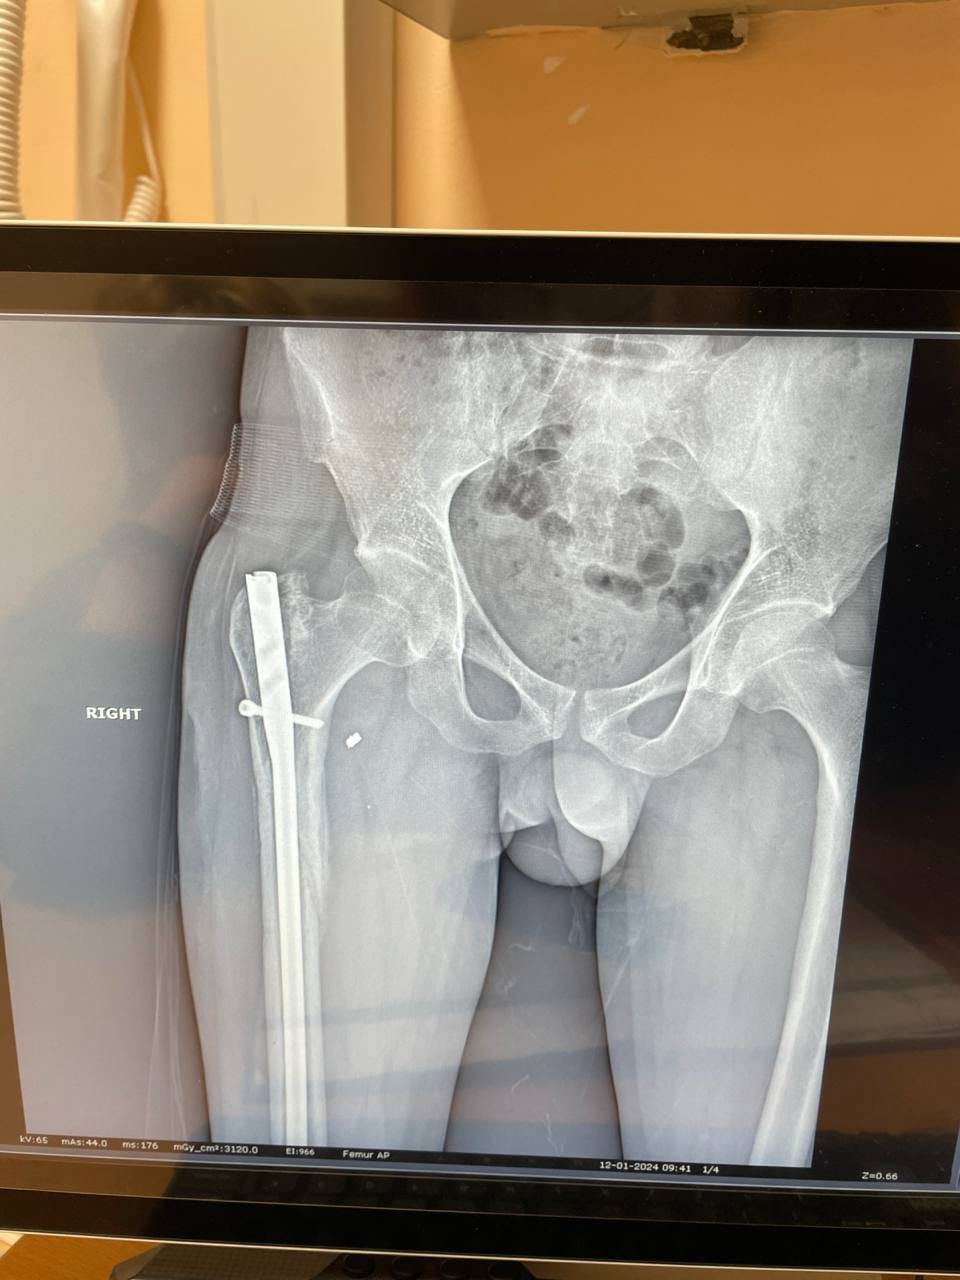

Друзі, знайомтеся: це Алік. Мій боєць, сапер, який отримав важкі поранення влітку минулого року під час штурмової операції південніше Бахмуту. Операція пішла невдало, групу накрили гради. Алік врятував кількох поранених бійців, надавав їм першу допомогу, але й сам зазнав серйозних ушкоджень.

Військовий третьої штурмової бригади Алік